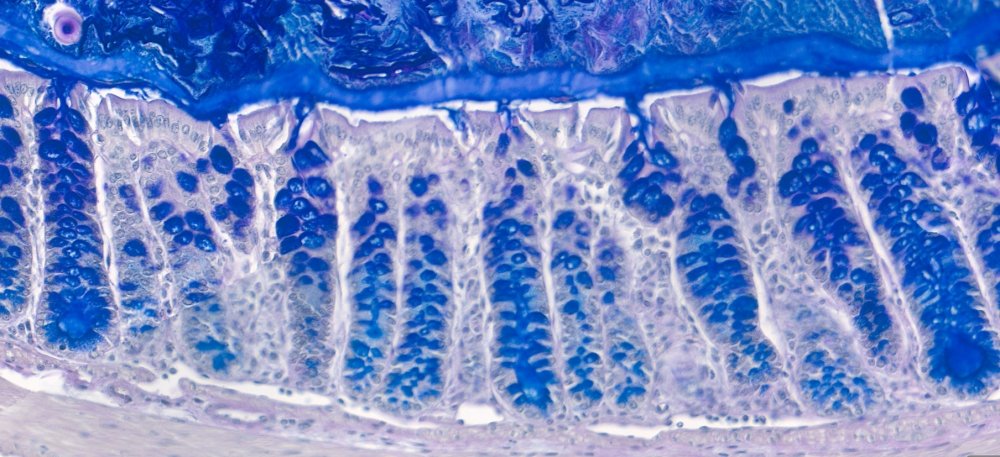

Efter transplantation av den mänskliga tarmfloran i möss och med hjälp av specialiserade metoder för att analysera slemfunktionen i tarmen, fann forskarna att funktionen av slemlagret stördes hos möss transplanterade med bakterier från människor som genomgått upprepade antibiotikakurer. Tillväxt av slem minskade, och slemlagret blev genomträngligt, vilket gjorde att bakterier kunde flytta sig närmare tarmslemhinnan.

– När vi studerade bakterierna som finns i tarmen mer i detalj, kunde vi se att bakterier som vi vet livnär sig på slemlagret fanns i större mängder i dessa möss. Detta stödjer ytterligare att tarmbakterierna har en roll när det gäller betydelsen för hur väl slembarriären fungerar, säger Rachel Feeney, doktorand på Institutionen för molekylärbiologi vid Umeå universitet.

Våra tarmbakterier är viktiga för att smälta mat och träna immunförsvaret, men deras aktivitet måste noggrant regleras av våra kroppar för att inte riskera vår hälsa. Tarmarna kantas av ett kontinuerligt växande slemlager som bakterier vanligtvis inte kan passera. Om tarmmiljön störs, till exempel av ändrad kost eller antibiotika, kan slembarriären förlora sin förmåga att fungera normalt. Bakterier kan då nå tarmslemhinnan och orsaka inflammation och kanske även bidra till utveckling av exempelvis inflammatorisk tarmsjukdom.

Vissa tarmbakterier ”äter” komponenter i slembarriären, vilket fysiskt gör lagret tunnare. Även om det är normalt i låga nivåer i den friska tarmen, kan överdrivet ”ätande” äventyra slembarriärens funktion.